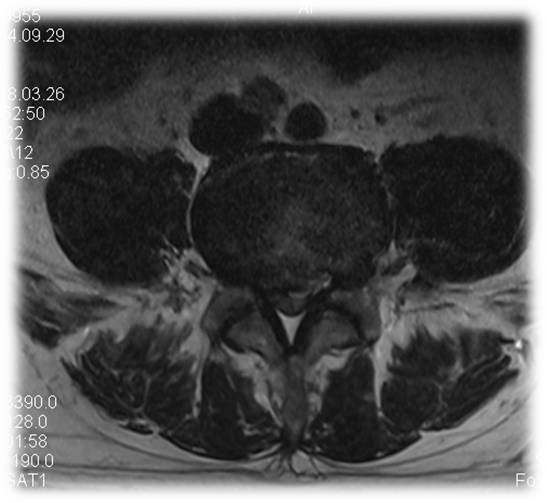

术前 图片2